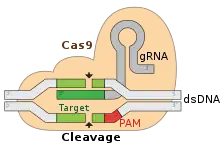

- A new study by researchers at Stanford University indicates the genetic engineering method known as CRISPR may trigger an immune response in humans, thus rendering it potentially ineffective in them.[19][20]

- University of Pennsylvania announces in the United States National Library of Medicine human clinical trials, that will encompass the use of CRISPR technology to modify the T cells of patients with multiple myeloma, sarcoma and melanoma cancers, to allow the cells to more effectively combat the cancers, the first of their kind trials in the US.[30][31]

- Medical researchers at the Gladstone Institutes discover a method of turning skin cells into stem cells, with the use of CRISPR.[42][43]

- Scientists from Purdue University and the Chinese Academy of Sciences report the use of CRISPR/Cas9 to develop a variety of rice producing 25-31% more grain than traditional breeding methods.[161]